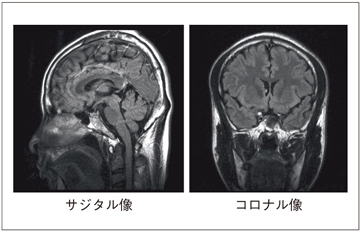

高度な位相補正処理と全方向の折返し除去対応により,任意の撮像断面を設定できます。図4に,RADAR-FLAIRによる頭部のサジタル像とコロナル像を示します。

図4 RADARの撮像断面例(頭部RADAR-FLAIR)